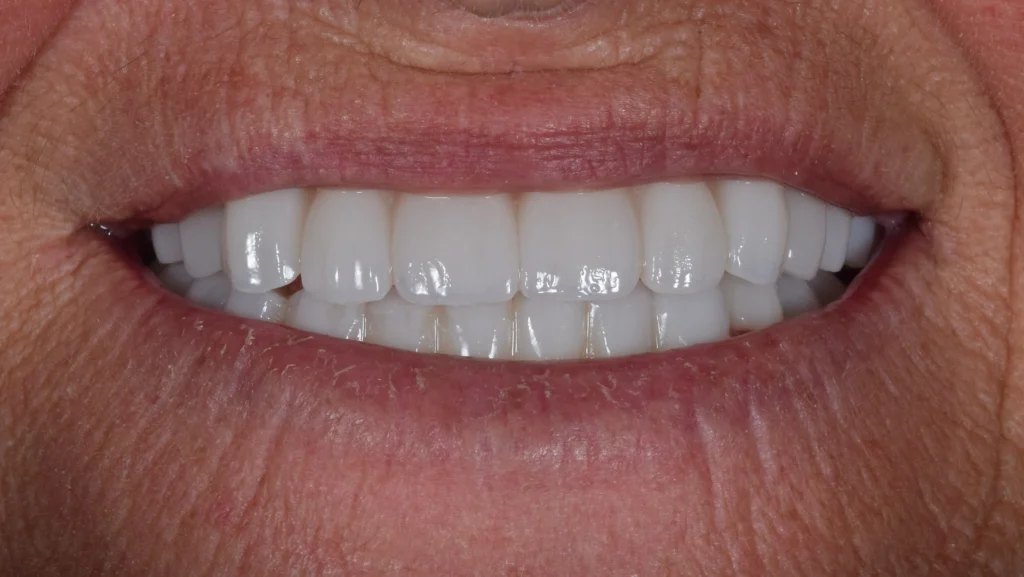

After 6 months of healing and osseointegration of the dental implants, the patient came back for her final restoration. The case was a difficult Class III with advancement of the lower jaw.

But using a digital workflow and detailed planning a total mouth reconstruction was made with an hybrid zirconia-titanium construction and zirconia crowns and bridges. A beautiful, new, functional and esthetic smile was provided for this lovely patient.